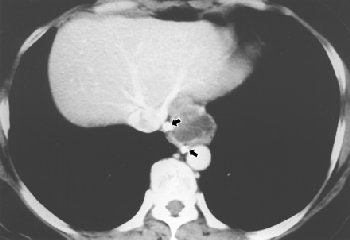

MRI

Pericardial abscess occurring as a complication of tuberculous pericarditis can be studied both on CT and MRI. Information on the location and extent of the pericardial abscess can be useful inputs for deciding the surgical approach and in selecting the optimal path for guided needle aspiration (Clinical Radiology, June 2004, Vol. 59:6, pp. 514-519).

![]() |

| Fifty-year-old woman with submucosal tuberculous abscess in esophagus. Esophageal endosonogram shows relatively well-demarcated heterogeneously hypoechoic mass (M) containing scattered echogenic debris in esophageal wall. Surrounding adventitia (arrowheads) appears somewhat irregular. Note small hypoechoic periesophageal lymph node (arrows) external relative to esophagus. L = fluid-filled esophageal lumen, P = center of probe, A = descending thoracic aorta. |

Imaging on MRI and CT have the advantage of being less operator-dependent, and are not limited by a poor acoustic window compared with echocardiography. MRI, in addition to having no radiation risk, is sensitive especially for detection of small effusions. However, MR findings do not provide any disease-specific image morphology.

| Fifty-year-old woman with submucosal tuberculous abscess in esophagus. Contrast-enhanced axial CT scan shows relatively well-marginated cystic mass at distal esophagus. Thick, partially calcified enhancing rim is noted at periphery of mass. Calcified small periesophageal lymph nodes (arrows) are adjacent to mass. Lee KH, Kim HJ, Kim KH, Kim HG, "Esophageal Tuberculosis Manifesting as Submucosal Abscess," (AJR 2003; 180: 1482-1483). |

Line scan diffusion-weighted MR images, as well as contrast-enhanced CT and esophageal endosonogram, can be used for diagnosis and evaluation of esophageal tuberculosis, which is relatively rare and found in less than 1% of patients who die of TB (AJR, May 2003, Vol. 180:5, pp. 1482-1483).